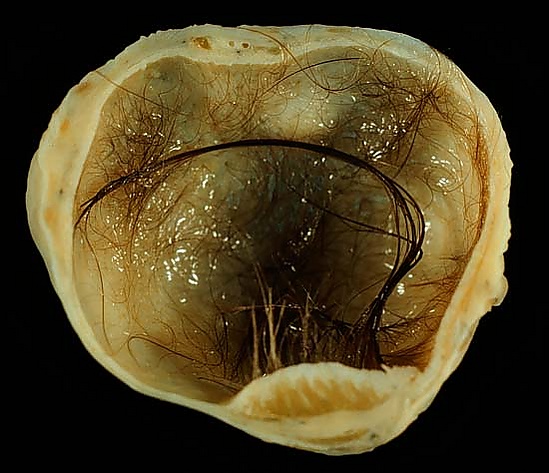

Дермоидная киста яичника

Дермоидная киста яичника (зрелая кистозная тератома яичника) — доброкачественная герминогенная опухоль, выстланная многослойным эпителием и заполненная желеобразным содержимым (зрелыми фрагментами производных эктодермы, эндодермы и мезодермы)[1][2].

Внутренняя поверхность кисты выстлана аналогом кожи с придатками (волосы, ногти, потовые и сальные железы). Содержимое 100 % кист — крошковидная беловатая масса, волосы и жир, 5,4 % — костная ткань, 2,7 % — хрящевая ткань, 2,7 % — участки нижней челюсти, иногда — фрагменты фиброзной и нервной ткани, кровеносных сосудов, зачатки глаза и клетки поджелудочной щитовидной или слюнной железы[1][2][5][6]. Скорость роста медленная — 1,8 мм/год[4].